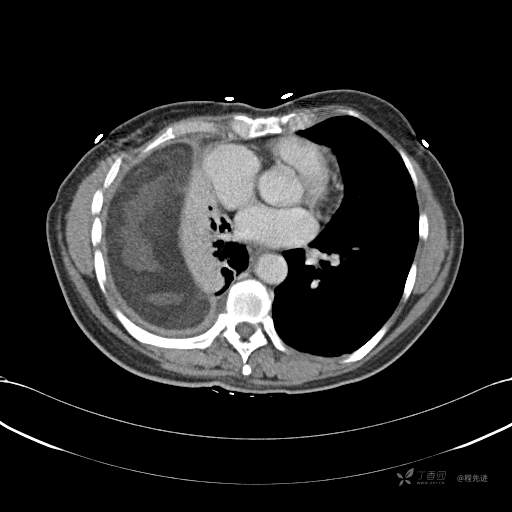

患者性别:女

患者年龄:51岁

简要病史:胸闷半年